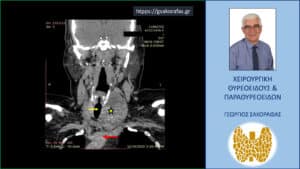

Καταδυόμενη βρογχοκήλη – αξονική τομογραφία σε κατά μέτωπο διατομή. Απεικονίζεται ο ευμεγέθης όζος (κίτρινος αστερίσκος) σε θέση κατάδυσης στο ανώτερο μεσοθωράκιο φθάνοντας στις παρυφές του αορτικού τόξου (κόκκινο βέλος) ανάμεσα από την έκφυση της ανωνύμου αρτηρίας και της αριστερής υποκλειδίου αρτηρίας, απωθώντας προς τα δεξιά την τραχεία (κίτρινο βέλος).